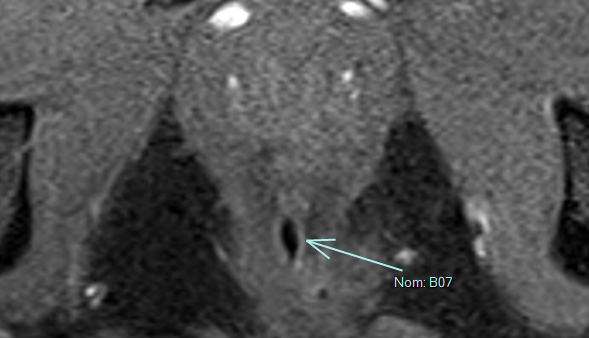

Séton

- Sorte d’élastique posé par le chirurgien

- Permet de drainer la fistule

- Placé dans l’orifice primaire du canal anal et sort par l’orifice de sortie.